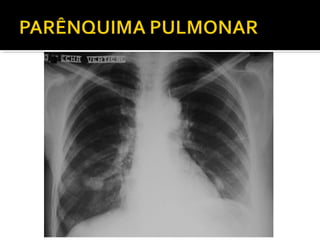

Este documento fornece parâmetros técnicos para realizar uma radiografia de tórax, incluindo posicionamento correto do paciente, dose adequada de radiação e estruturas anatômicas a serem avaliadas, como coração, pulmões, pleura, diafragma e ossos do tórax.